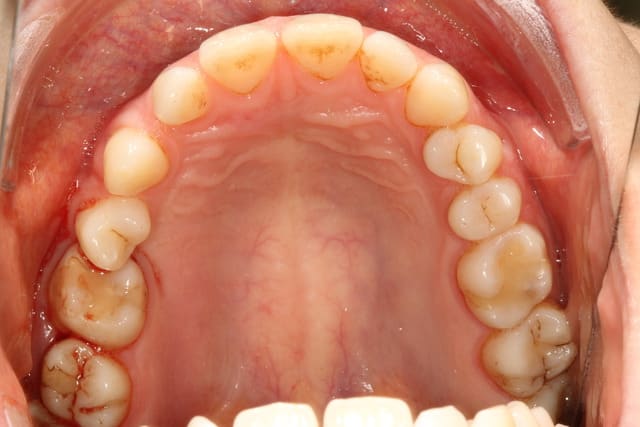

elle consulte pour une inflammation chronique secteur 2..

le panoramique est claire.. embouteillage entre 25, 26 et 65.

que proposez vous pour régler cette situation??

extraction 26 +65 et c'est tout?

extraction 26 65 et 25